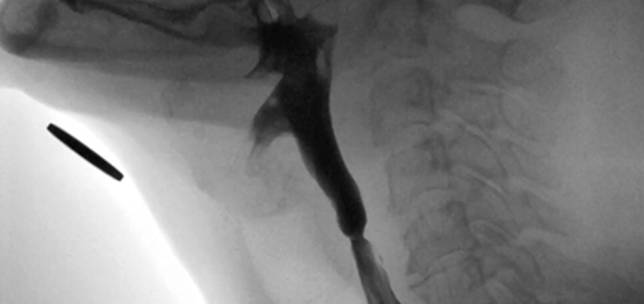

Dysphagia in complex laryngology – maintaining the balance